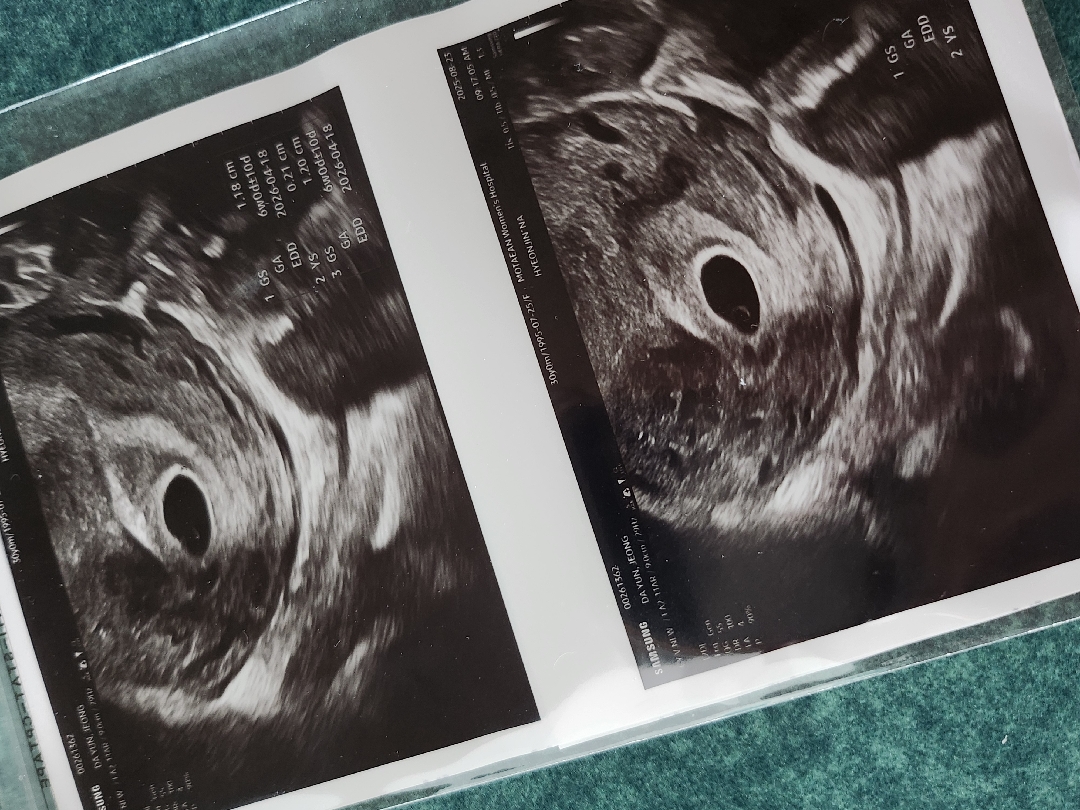

5주차 아기집

마지막 생리일은 7월 20일이고 몸이 안좋아서 임테기했더니 선명한 두줄보고 병원갔어요. 병원에서 아기집이 안보일수도 있다고 안보이면 피검사로 임신 확인하시겠다고 하셨는데 아기집+난황까지 보고 왔어요! 너무 신기해요~ 이제 심장소리 들으러 다음주에 가보려고요! 꼭 들었으면 좋겠어요